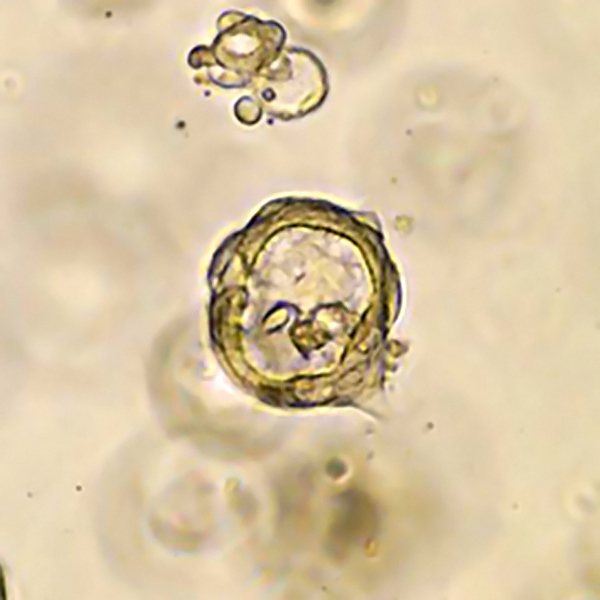

Organoids are a long-term culture system which allow cells to be grown in specialised 3D culture conditions that maintain the stem cell population as well as much of the cell/tissue architecture found in vivo. Cancer organoid models have been shown to recapitulate features of the original tissue/tumour and can model clinically relevant drug responses. Through generating large numbers of molecularly characterised organoid models, and performing drug sensitivity screens, we aim to identify new cancer treatments.

As part of the HCMI, the Sanger Institute has joined forces with Cancer Research UK (CRUK) to derive hundreds of organoid cell models from colon, oesophageal, pancreatic, lung, breast and ovarian cancers. These models are being generated from patient samples taken at the time of biopsy or surgical resection and are being mae availabel through the third-party repository ATCC https://www.lgcstandards-atcc.org/hcmi?geo_country=gb.